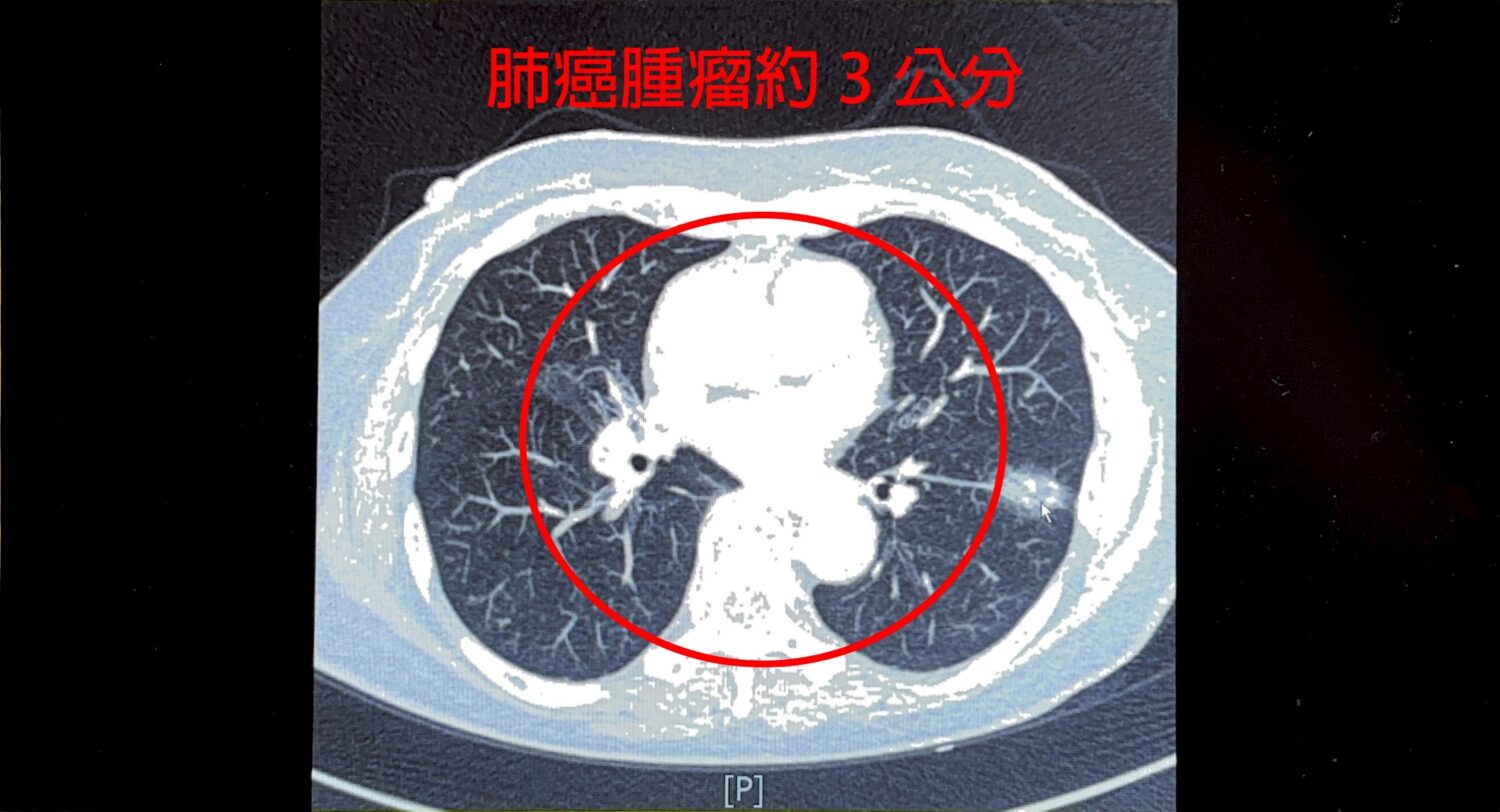

【警政時報 張家燁/新竹報導】一位75歲女性平時不菸不酒,今年於健康檢查安排LDCT肺癌篩檢,意外發現左下肺葉近3公分惡性腫瘤,求診中國醫藥大學新竹附設醫院胸腔外科謝義山醫師,經醫病溝通後,執行達文西微創手術,歷經4小時完成切除,病患術後三天順利出院,恢復情況良好。

謝義山醫師指出,患者十多年前曾罹患肺結核,導致肺部縱膈淋巴結硬化並與血管沾黏,手術中稍有不慎恐大出血,透過達文西機械手臂輔助,順利完成血管分離結紮,最終僅200cc出血,展現精準醫療優勢,術後建議病患逐步恢復日常,兩週可輕便活動,2至3個月後再進行重度運動。

謝醫師提醒,曾感染肺結核患者因肺部殘留病灶,罹患肺癌風險較一般人高出40至200倍,台灣女性肺癌患者中,80%至90%為不菸不酒族群,顯示基因遺傳及肺部結節也是重要風險因子,而有結核病史或家族史的女性,務必每年接受低劑量胸部電腦斷層篩檢,早期發現才能提高治癒率,肺癌初期常無明顯症狀,但若出現慢性咳嗽、咳血、胸痛、聲音沙啞、不明體重下降或反覆肺炎,應及早就醫。